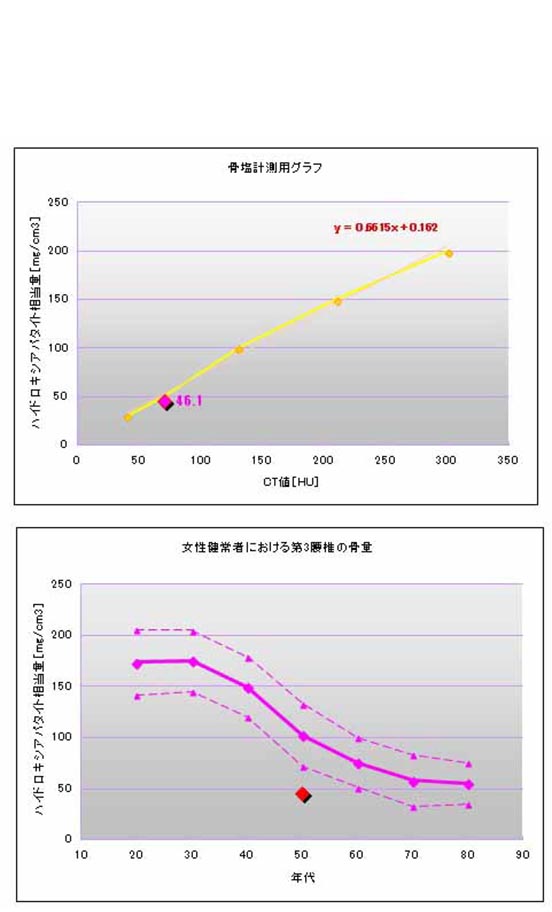

- 骨密度